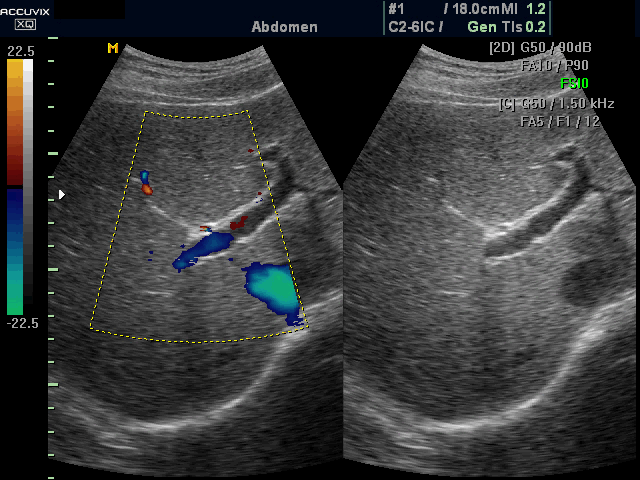

Ultraschall der Bauchregion

Die Sonographie(Ultraschall) ist eine schonende, risiko- und schmerzfreie Untersuchungsmethode. Insbesondere Erkrankungen des Bauchraumes ist die Sonografie des Abdomens (Ultraschall Bauch) fester Bestandteil der moderner Diagnostik. Der Ultraschall ermöglicht es uns, die Bauchorgane zu beurteilen und Erkrankungen oder Veränderungen zu erkennen.